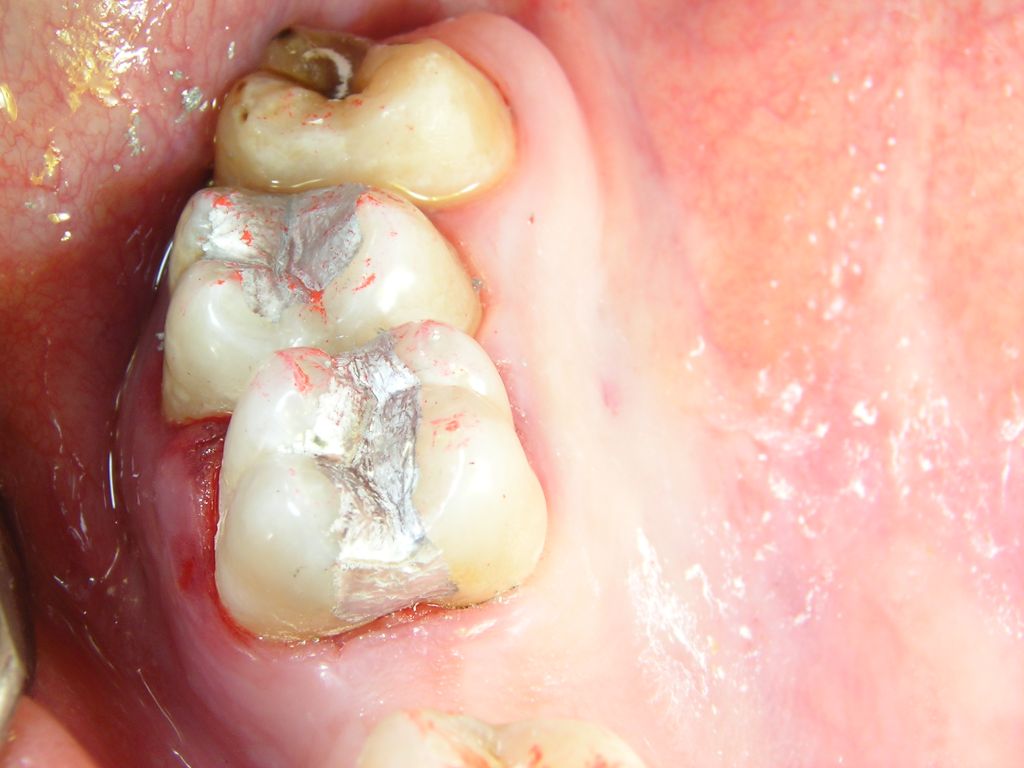

1 frische, 2 ältere Füllungen, Fissurenversiegler

Die Füllungen links wären auch in Composite gut vertretbar gewesen, die Füllungen rechts halten in Amalgam sicher länger als in Composite. Diese Amalgamfüllungen sind alle im Oberkiefer und im Alltag nicht sichtbar.